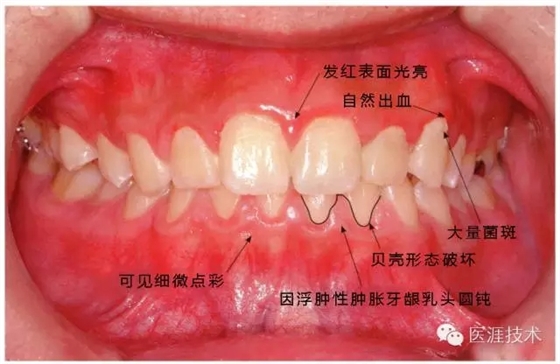

14歲男性牙齦炎的臨床圖像

14歲男性。刷牙狀態(tài)不佳。整顎浮腫性發(fā)紅、腫脹且刺激出血。牙頸部有早期齲(白斑)。